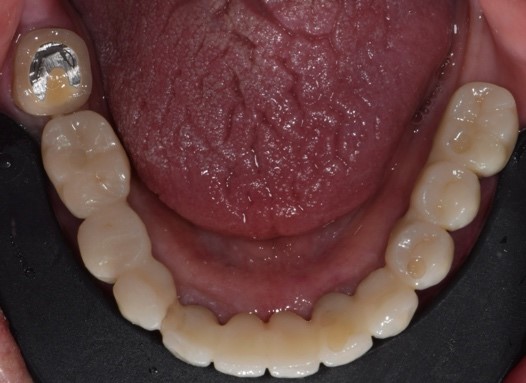

Protesi finale

Fig. 6(a)

Protesi finale 2

Fig. 6(b) Protesi finale.

I restauri si adattavano perfettamente, poiché il design dell'abutment iPhysio® aveva modellato i tessuti molli in modo così predicibile da poter essere riprodotto digitalmente sul profilo di emergenza della protesi finale (Fig. 7 a,b,c,d,e,f).